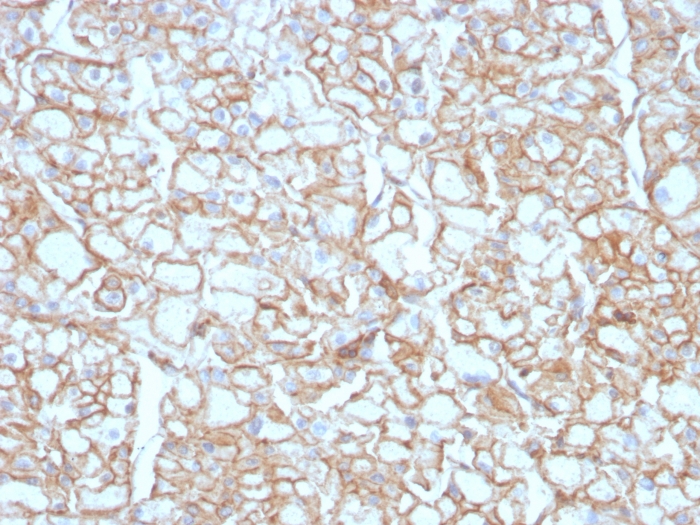

Formalin-fixed, paraffin-embedded human Lung SqCC stained with PD-L1 Recombinant Rabbit Monoclonal Antibody (PDL1/4451R).

PD-L1 is a checkpoint regulator in immune cells, it is expressed on immune or non-hematopoietic cells. Expression of the protein is seen during pregnancy where it has a role in suppressing the immune system. PD-L1 induces an inhibitory signal in activated T-cells and promotes T-cell apoptosis. It is overexpressed in a number of different cancers where it is believed to play a significant role in the cancer s ability to evade the immune system.